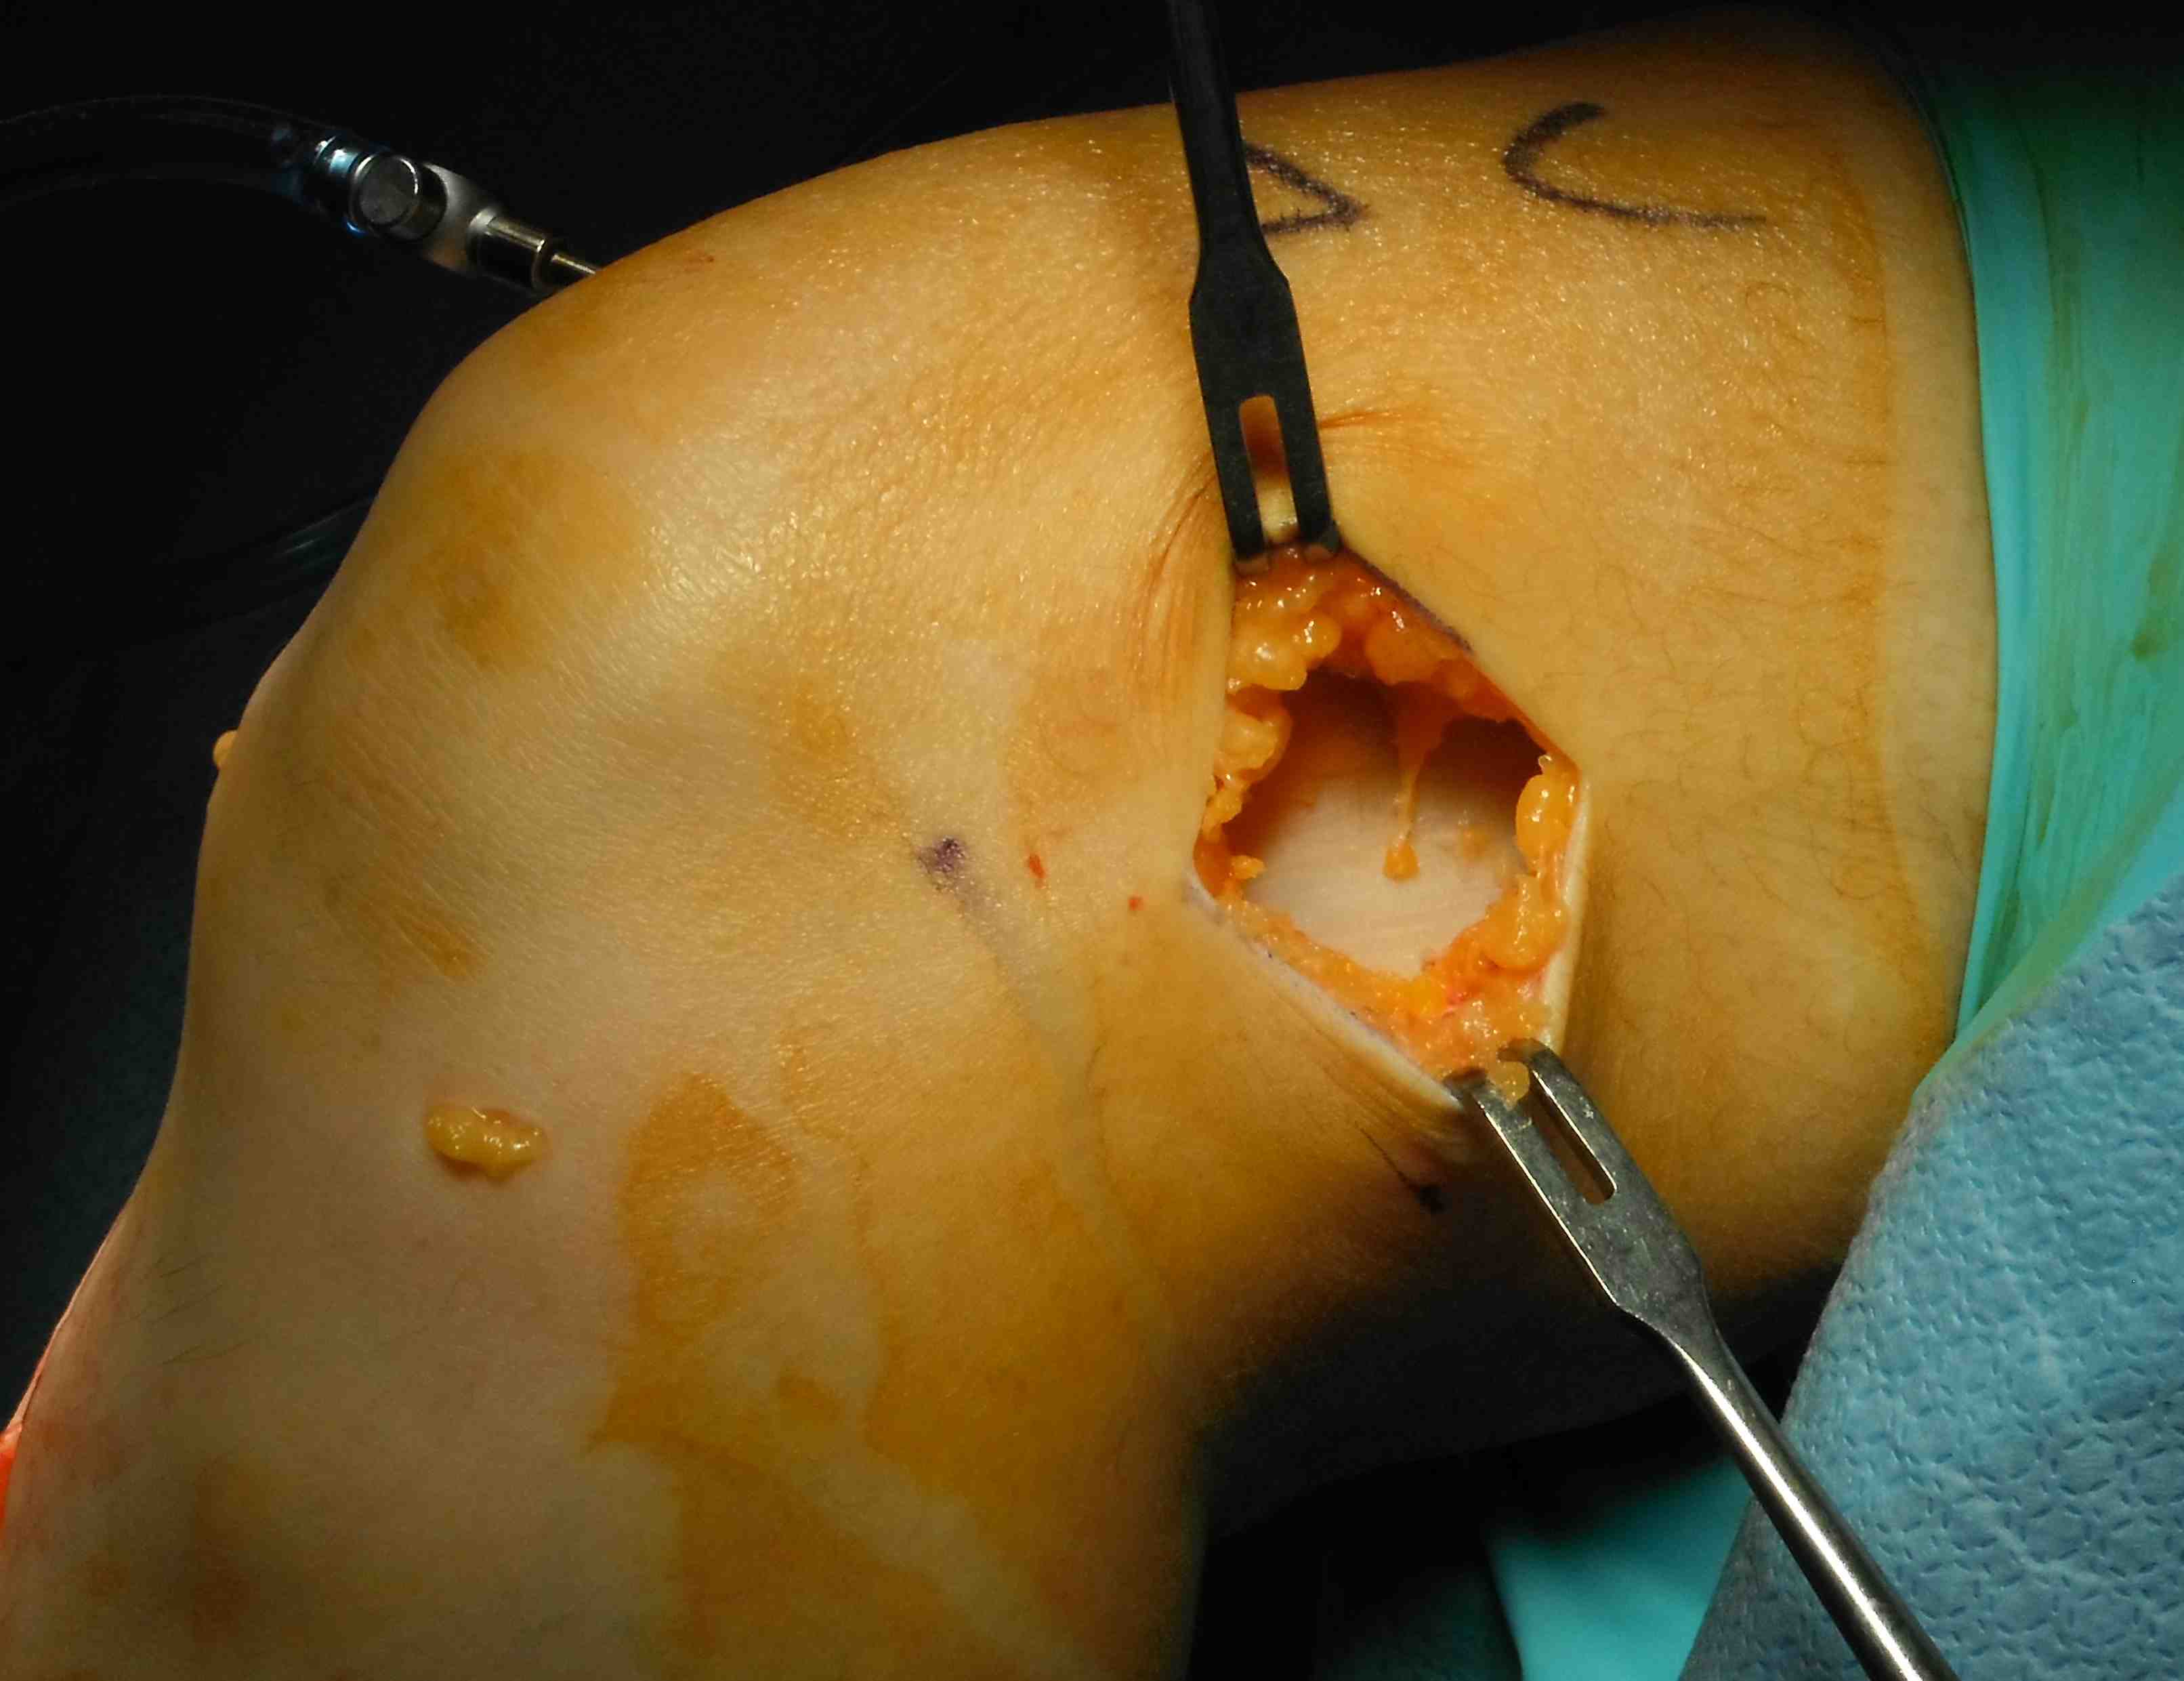

Need to make second incision in ITB

- pass graft anteriorly

- so can staple to femur